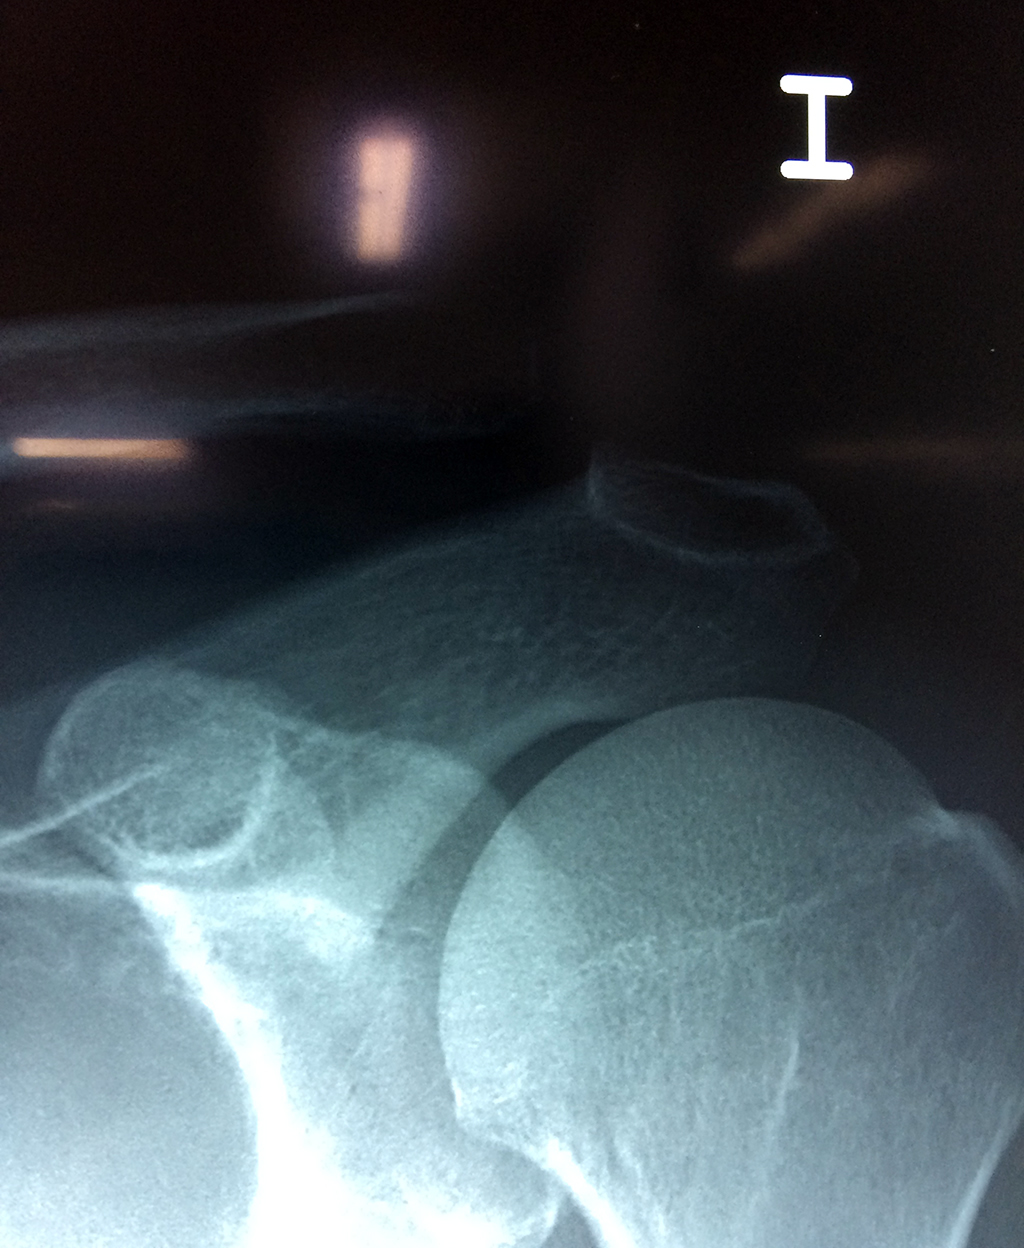

Cirugías de Húmero - Clavícula

La clavícula es un hueso largo, con forma de "S" itálica, situado en la parte anterosuperior del tórax. Junto con la escápula forman la cintura escapular. Se puede palpar por toda su longitud y se extiende del esternón al acromion de la escápula, siguiendo una dirección oblicua lateral y posterior.

Se considera el único medio de unión entre el miembro superior y el tórax. A pesar de su aspecto, similar al de un hueso largo, posee una estructura semejante a la de un hueso plano, ya que carece de epífisis y de diáfisis, lo que la harían entrar dentro de la clasificación de hueso largo. Carece de un canal medular propiamente dicho.